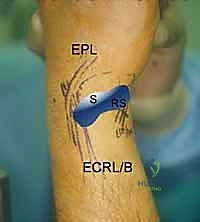

5. The 1-2 Portal

- Location: This portal lies between the first and second dorsal extensor compartments.

- Anatomy:

- First Compartment: Contains the abductor pollicis longus (APL) and extensor pollicis brevis (EPB) tendons.

- Second Compartment: Contains the extensor carpi radialis longus (ECRL) and extensor carpi radialis brevis (ECRB) tendons.

- Neurovascular Risks: The superficial radial nerve (SRN) is highly vulnerable in this region. Its branches can be quite variable. Meticulous blunt dissection and careful palpation of the tendons are crucial.

- Function: Used less frequently than 3-4 or 4-5, but provides an excellent view for radial styloidectomy, visualizing the radioscaphoid joint, and addressing specific pathologies on the radial side.